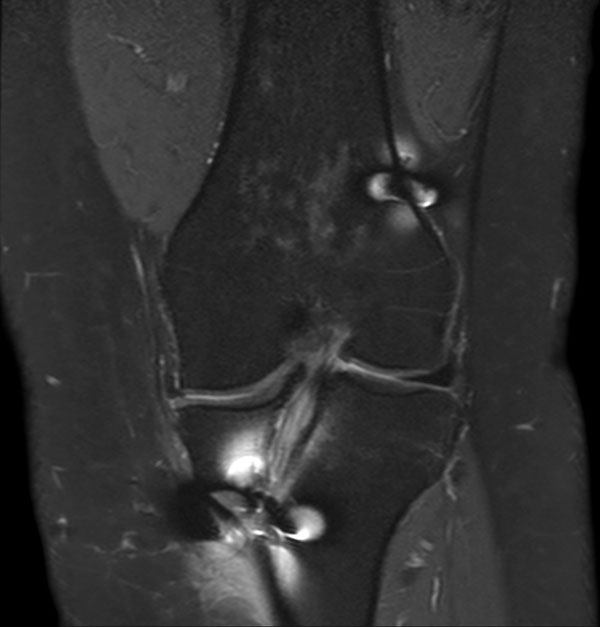

Coronal STIR aTSE (MARS)